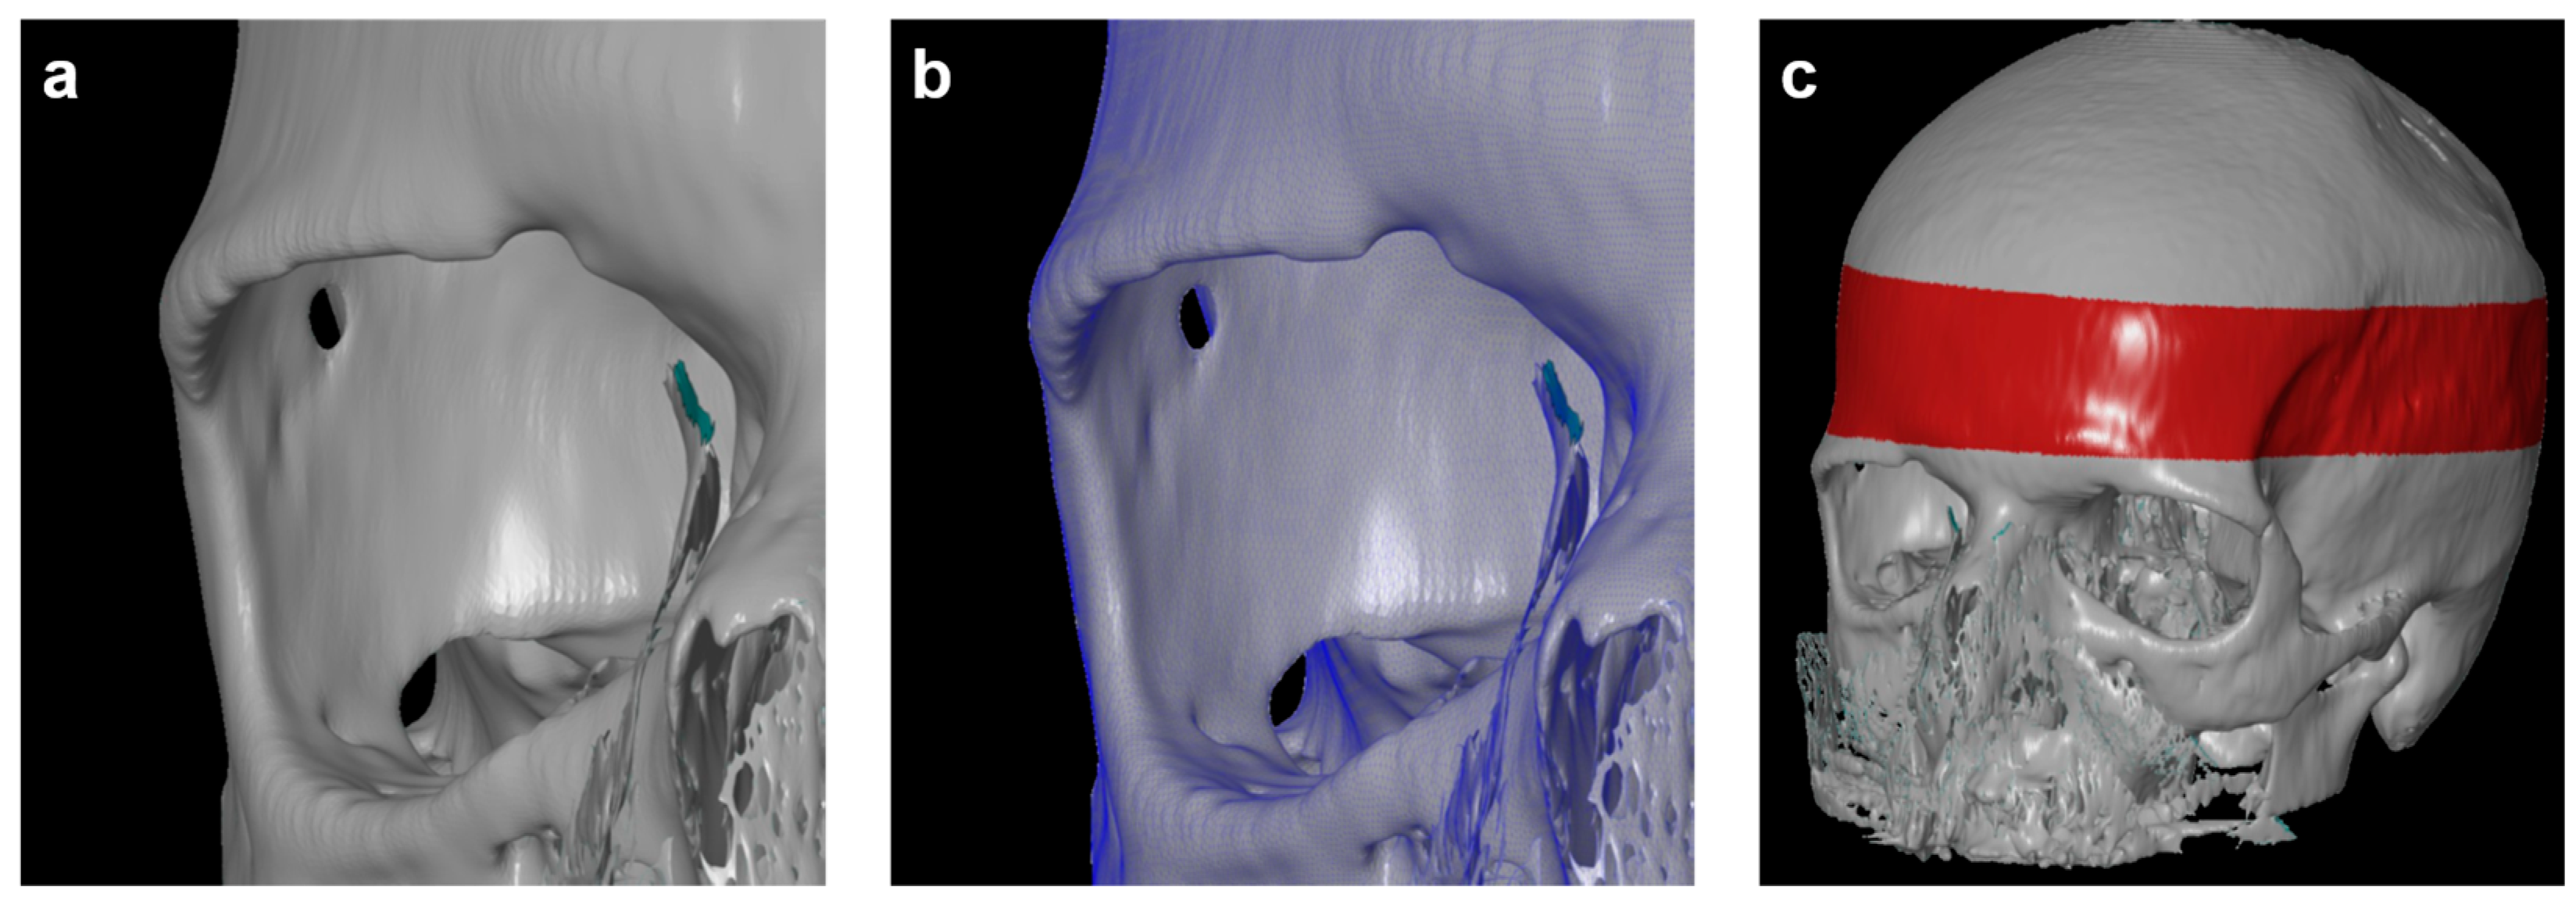

3.2. Descriptive Imaging Reports before and after 3D Reconstruction

3.4. Three-Dimensional (3D) Measurements of Biparietal Thinning